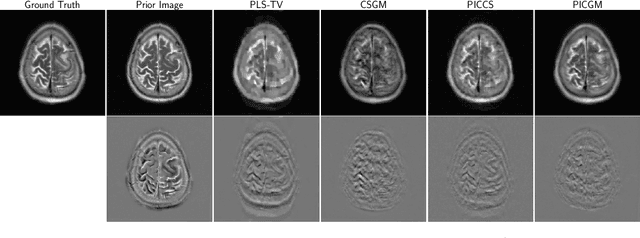

Obtaining an accurate and reliable estimate of an object from highly incomplete imaging measurements remains a holy grail of imaging science. Deep learning methods have shown promise in learning object priors or constraints to improve the conditioning of an ill-posed imaging inverse problem. In this study, a framework for estimating an object of interest that is semantically related to a known prior image, is proposed. An optimization problem is formulated in the disentangled latent space of a style-based generative model, and semantically meaningful constraints are imposed using the disentangled latent representation of the prior image. Stable recovery from incomplete measurements with the help of a prior image is theoretically analyzed. Numerical experiments demonstrating the superior performance of our approach as compared to related methods are presented.